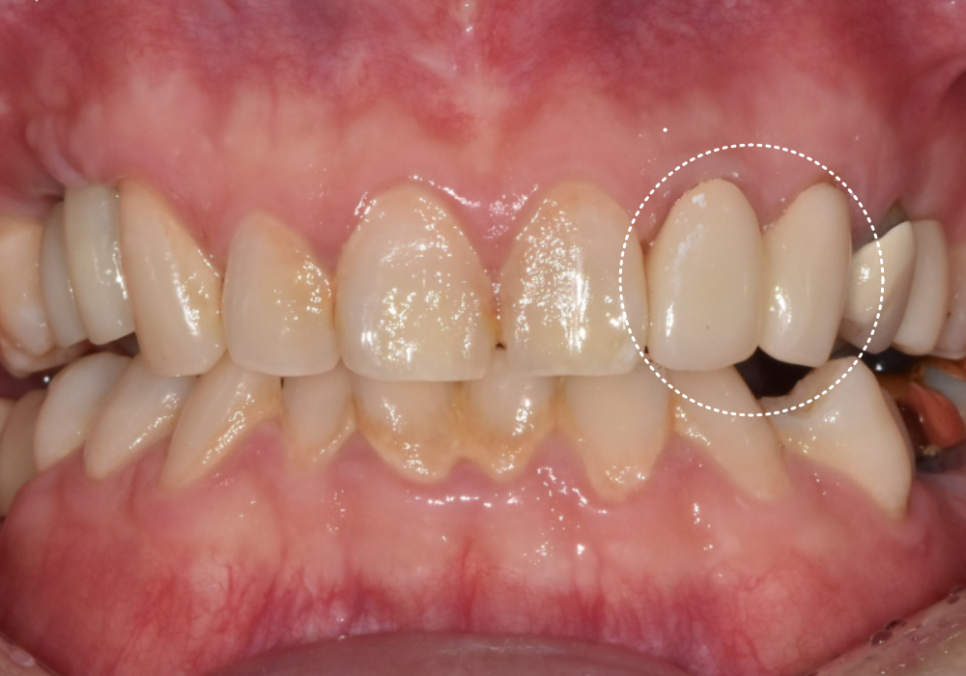

깨끗해진 신경관을

생체 친화적인 재료로 꼼꼼히 메운 뒤,

240424

지르코니아 크라운을 씌워

치료를 마무리했습니다. ^^

환자분께서 느끼시는 증상도 많이 좋아지셔서

신경치료를 마무리해드렸어요.